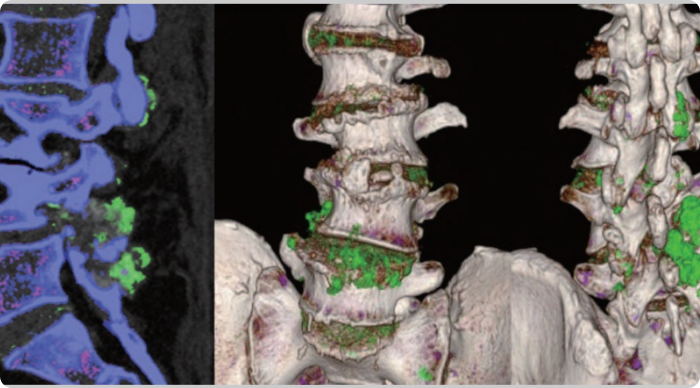

Dual Energy CT scan of uric acid buildup in foot at baseline

MIRROR RCT AT BASELINE

DECT image of urate buildup from a patient in MIRROR RCT.2

DECT, dual-energy computed tomography.

The primary endpoint in MIRROR RCT was defined as the proportion of patients achieving and maintaining an sUA level of <6 mg/dL for at least 80% of the time during Month 6; 71% of patients receiving KRYSTEXXA with methotrexate (n=100) vs 39% of patients receiving KRYSTEXXA alone (n=52) met the primary endpoint (P<0.0001).3

Tophi resolution was a secondary endpoint that was defined as 100% resolution of at least one target tophus, no new tophi appearing, and no single tophus showing progression at Month 12; 54% (28/52) of patients receiving KRYSTEXXA with methotrexate achieved tophi resolution vs 31% (9/29) of patients receiving KRYSTEXXA alone (P=0.048).3,4

Side by side Dual Energy CT scans showing uric acid buildup in foot before and after KRYSTEXXA with methotrexate treatment

MIRROR RCT FROM BASELINE TO 52 WEEKS

Feet images are DECT images of one patient taken from MIRROR RCT.2 Individual results may vary. Optimal treatment duration has not been established.3 Best results were seen at 6-12 months.3 Analysis is exploratory and has not been adjusted for multiple comparisons. No clinical or statistical conclusions can be drawn.

The MIRROR RCT was a 52-week, randomized, double-blind, placebo-controlled trial, conducted in adult patients with chronic gout refractory to conventional therapy, to evaluate administration of KRYSTEXXA (8 mg Q2W) coadministered with 15 mg/week oral methotrexate and 1 mg/day oral folic acid (n=100) vs KRYSTEXXA with placebo (n=52).3,5